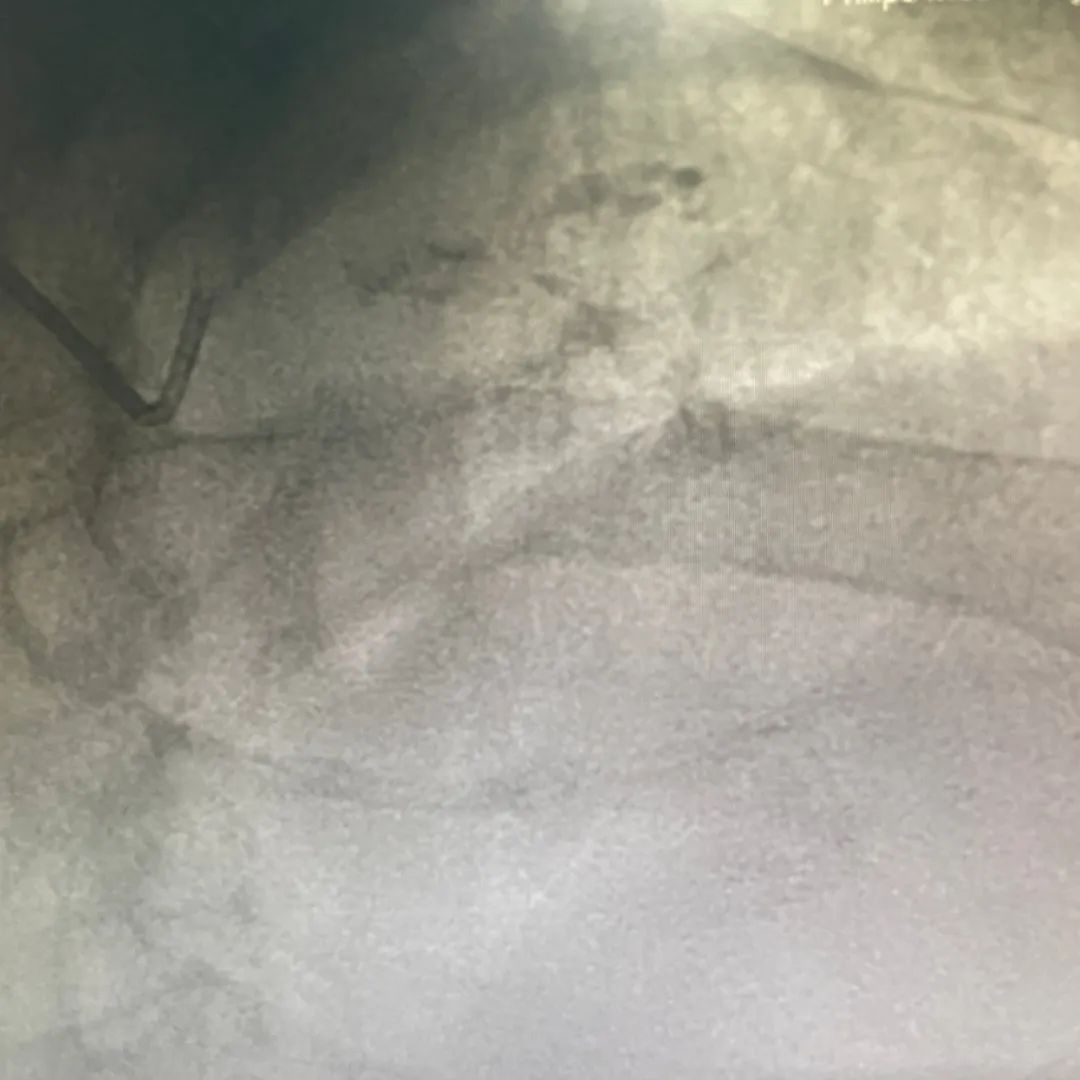

经桡动脉送入7F EBU3.5指引导管到位,Sion-blue指引导丝通过狭窄病变并送达前降支远端,1.5x15mm球囊、2.0x15mm球囊预扩之后复查造影示狭窄及血流稍改善。拟OCT评估钙化情况,但由于操作过程中患者缺血症状明显,于是决定先植入支架:前降支-左主干依次串联置入3.0x22mm及3.5x22mm Integrity支架2枚,高压后扩张呈现“狗骨头”现象,OCT提示支架膨胀不全,支架周边>180°钙化。

遂使用3.5-12mm Shockwave冲击波球囊4atm共5个周期处理后支架膨胀良好。进一步3.5mm/4.0mm低顺应性球囊后扩修饰。